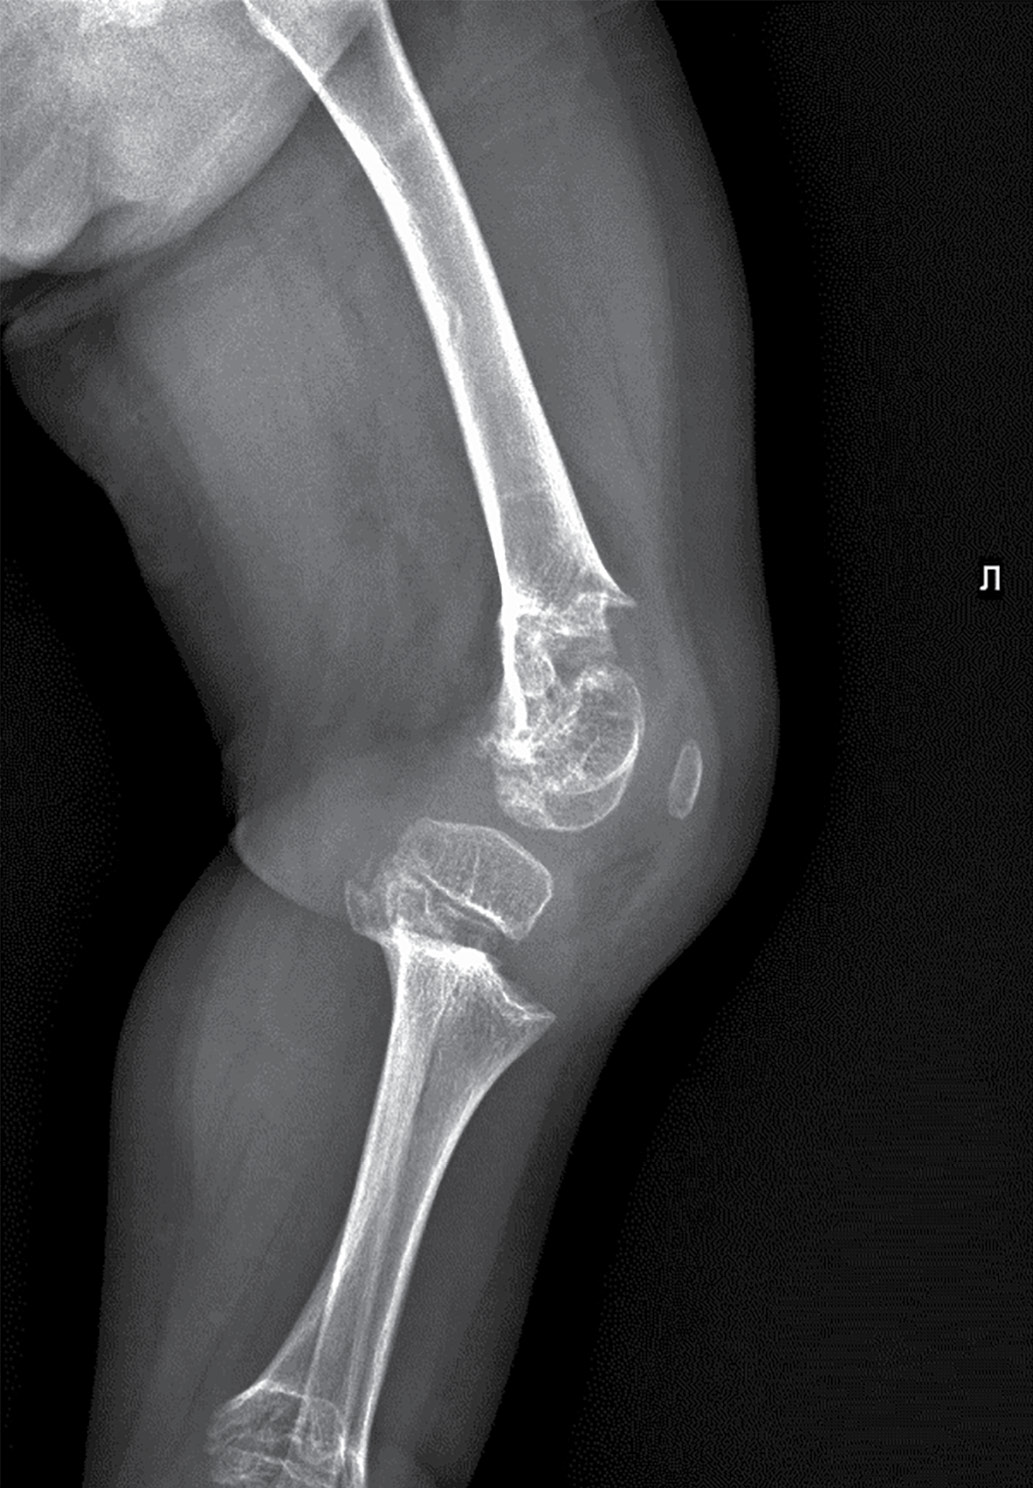

В биохимическом анализе крови клинически значимых изменений нет: кальций общий — 2,49 ммоль/л, кальций ионизированный — 1,28 ммоль/л, фосфор неорганический — 1,89 ммоль/л. В гормональном профиле уровень ИФР-1 соответствует возрастной норме — 81,7 нг/л (18,2–172,0). По данным рентгенографии нижних конечностей, в прямой проекции выявлена выраженная варусная деформация коленных суставов. Метаэпифизы всех костей, образующих правый и левый коленные суставы, расширены, вздуты. Соотношения в суставах неправильные (больше — в правом суставе). Суставные поверхности неровные, нечеткие, суставные щели неравномерные, расширены (рис. 1–2).

Рисунок 1. Рентгенография коленного и тазобедренного суставов в прямой проекции.